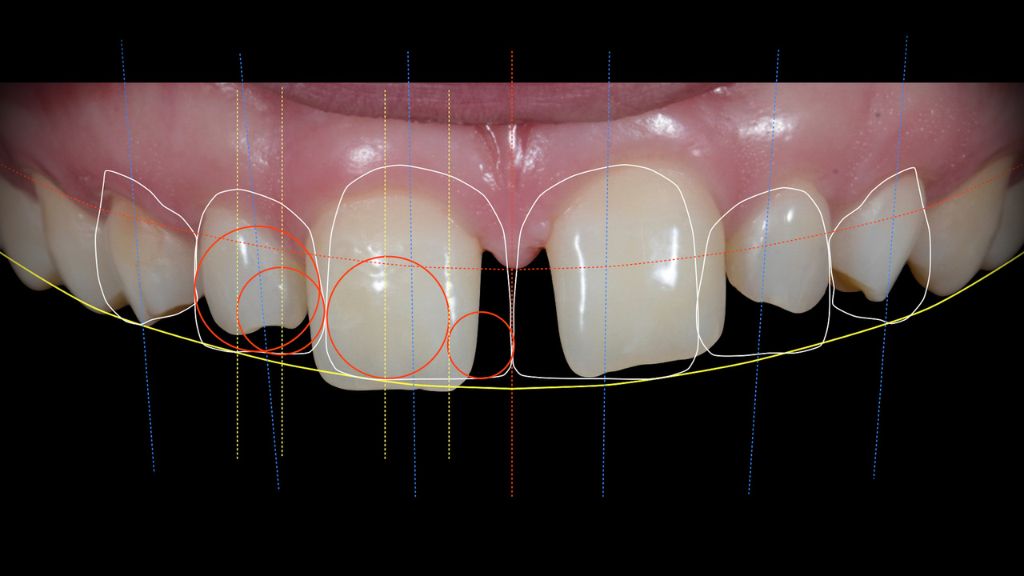

La Dra. Gil utiliza tecnología de última generación, como el diseño de sonrisa, para ofrecer resultados precisos y personalizados, asegurando que cada sonrisa sea única y refleje la esencia del paciente. Su enfoque integral combina ciencia y arte para lograr sonrisas naturales que no solo mejoran la estética, sino también la autoestima y el bienestar general.

Por otro lado, el uso de tecnología avanzada como el diseño de sonrisa 3D permite a los pacientes visualizar el resultado final antes de comenzar el tratamiento, brindando mayor confianza y seguridad durante todo el proceso.

En la clínica de la Dra. Carolina Gil, el uso de tecnología avanzada es fundamental para garantizar resultados precisos y personalizados en el diseño de sonrisa. Las innovaciones tecnológicas permiten un enfoque más detallado y controlado, asegurando que cada paciente obtenga una sonrisa que se adapte perfectamente a sus rasgos faciales y necesidades estéticas. Dos de las principales herramientas que se emplean en este proceso son el escáner digital de sonrisa y el diseño de sonrisa 3D.

Diseño de Sonrisa 3D: Visualización del Resultado Final

El diseño de sonrisa 3D es una herramienta digital que permite a los pacientes visualizar cómo será su sonrisa antes de que comience el tratamiento. Con este software, se crea un modelo digital del resultado esperado, permitiendo ajustes y personalizaciones antes de cualquier intervención. Esto brinda a los pacientes mayor tranquilidad y confianza, ya que pueden ver cómo su sonrisa cambiará y asegurarse de que el resultado cumpla con sus expectativas.

Beneficios del diseño de sonrisa 3D:

- Resultados predecibles: Los pacientes pueden visualizar el resultado final, lo que asegura una mayor satisfacción.

- Personalización total: Cada diseño se adapta a las características faciales y dentales del paciente, logrando un resultado natural y armonioso.

- Menor tiempo de tratamiento: Al previsualizar el resultado, el equipo puede planificar con mayor precisión, reduciendo el tiempo necesario para lograr la sonrisa perfecta.

El uso de estas herramientas avanzadas en la clínica de la Dra. Carolina Gil asegura que el tratamiento de diseño de sonrisa sea lo más cómodo, eficiente y predecible posible, garantizando resultados de alta calidad y una sonrisa que transforma la vida de los pacientes.

Elegir a la profesional adecuada para tu diseño de sonrisa es fundamental para garantizar resultados de alta calidad. La Dra. Carolina Gil, con más de 10 años de experiencia en odontología estética y cirugía maxilofacial, se ha consolidado como una de las líderes en odontología cosmética en Bogotá. Su enfoque se basa en combinar tecnología avanzada, como el escáner digital de sonrisa y el diseño de sonrisa 3D, con una atención personalizada para cada paciente, asegurando resultados naturales que armonizan con los rasgos faciales y las necesidades individuales.

Cada tratamiento se define durante la consulta de valoración, donde la Dra. Carolina Gil y el Dr. Carlos Castro evalúan la situación dental del paciente, discuten sus expectativas y diseñan un plan que garantice una sonrisa natural y armoniosa. La tecnología de diseño de sonrisa 3D permite visualizar el resultado antes de iniciar el tratamiento, ofreciendo una visión clara y precisa del resultado final.